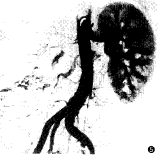

7例中有4例进行了DSA检查,其中3例肾性高血压患者2例见患肾动脉细小,实质期患肾仅见少许染色(图5)。1例多发性大动脉炎患者DSA示降主动脉膈段一明显狭窄,肋间动脉、膈动脉增粗并见迂曲增粗的侧支循环,右肾开口处狭窄,肾动脉下至第3~4腰椎水平间腹主动脉段狭窄,腰动脉增粗(图6、7)。

图1 团注试验剂量后肾动脉水平降主动脉内信号强度-时间曲线 图2、3 肾性高血压患者。平扫时右肾体积明显缩小,DCE-MRA示右肾动脉细小,分为3支,发自主动脉 图4 大动脉炎患者。降主动脉膈段明显狭窄,右膈动脉增粗,肾动脉水平以下节段性不规则狭窄,双肾动脉开口处狭窄 图5 同图2病例。血管造影示右肾动脉细小,分为3支,右肾实质未显影 图6、7 同图4病例。血管造影示降主动脉膈段明显狭窄,右膈动脉及肋间动脉增粗迂曲,肾动脉水平以下节段性狭窄,右肾动脉开口狭窄